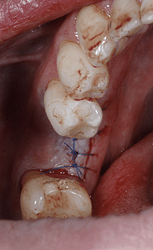

( after 3 months, implant was uncovered but the buccal cervical bone is missing , there is no denture use at all and the buccal wall just disappeared. there was no bone graft or membrane used when the implant was placed)

at the end, Ethoss, beta-TCP was grafted and moulded around the implant to close again.